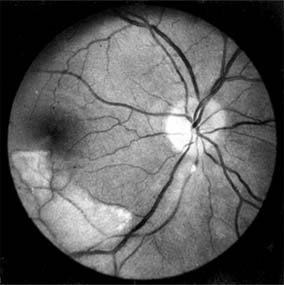

In contrast, elderly patients with arteriosclerotic vessels are unable to respond in this manner, and their vessels are thus protected by the arteriosclerosis. It is for this reason that elderly patients seldom exhibit florid hypertensive retinopathy (Figure 15-11).

Figure 15-11

Figure 15-11: Accelerated hypertension. Fluorescein angiogram in an elderly wom.an showing marked arteriolar constriction and irregularity but few signs of florid retinopathy.